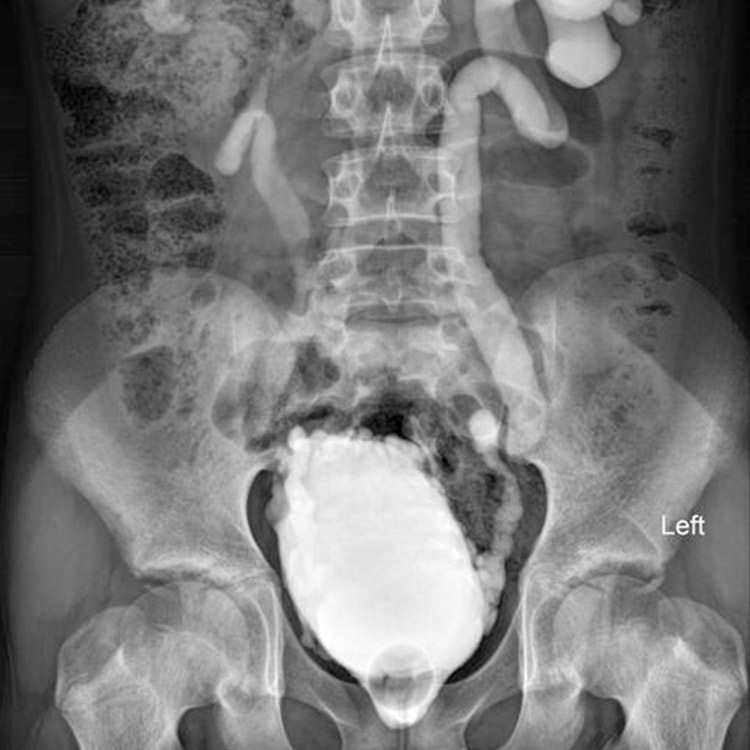

Modern radyolojik görüntüleme, hastalıkların net ve güvenilir şekilde değerlendirilmesini sağlar. Doğru tanı; gereksiz işlemlerin önüne geçer, tedavi sürecini hızlandırır ve hastaya güven verir.